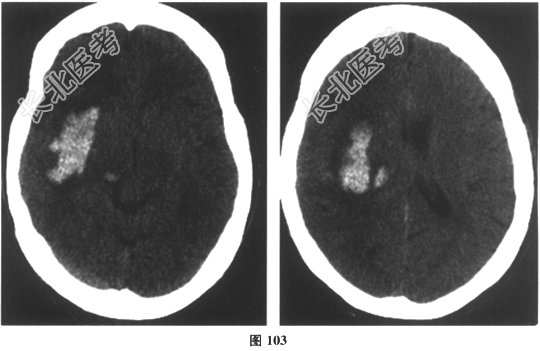

- 简答题5、[提示]患者继续降压药物治疗,在半年随访中,血压稳定在(140~150)/(70~80)mmHg。此后自行停用降压药物。1年后的某天清晨,患者在家中突感剧烈头痛,恶心、呕吐胃内容物,左侧肢体不能活动,急诊发现BP190/105mmHg,意识清楚,双眼向右侧凝视,左侧肢体肌力0级,肌张力消失,针刺感消失,左侧巴宾斯基征阳性。此时首选检查为

- 简答题6、[提示]急查颅脑CT,结果如图103所示。

该患者诊断为?